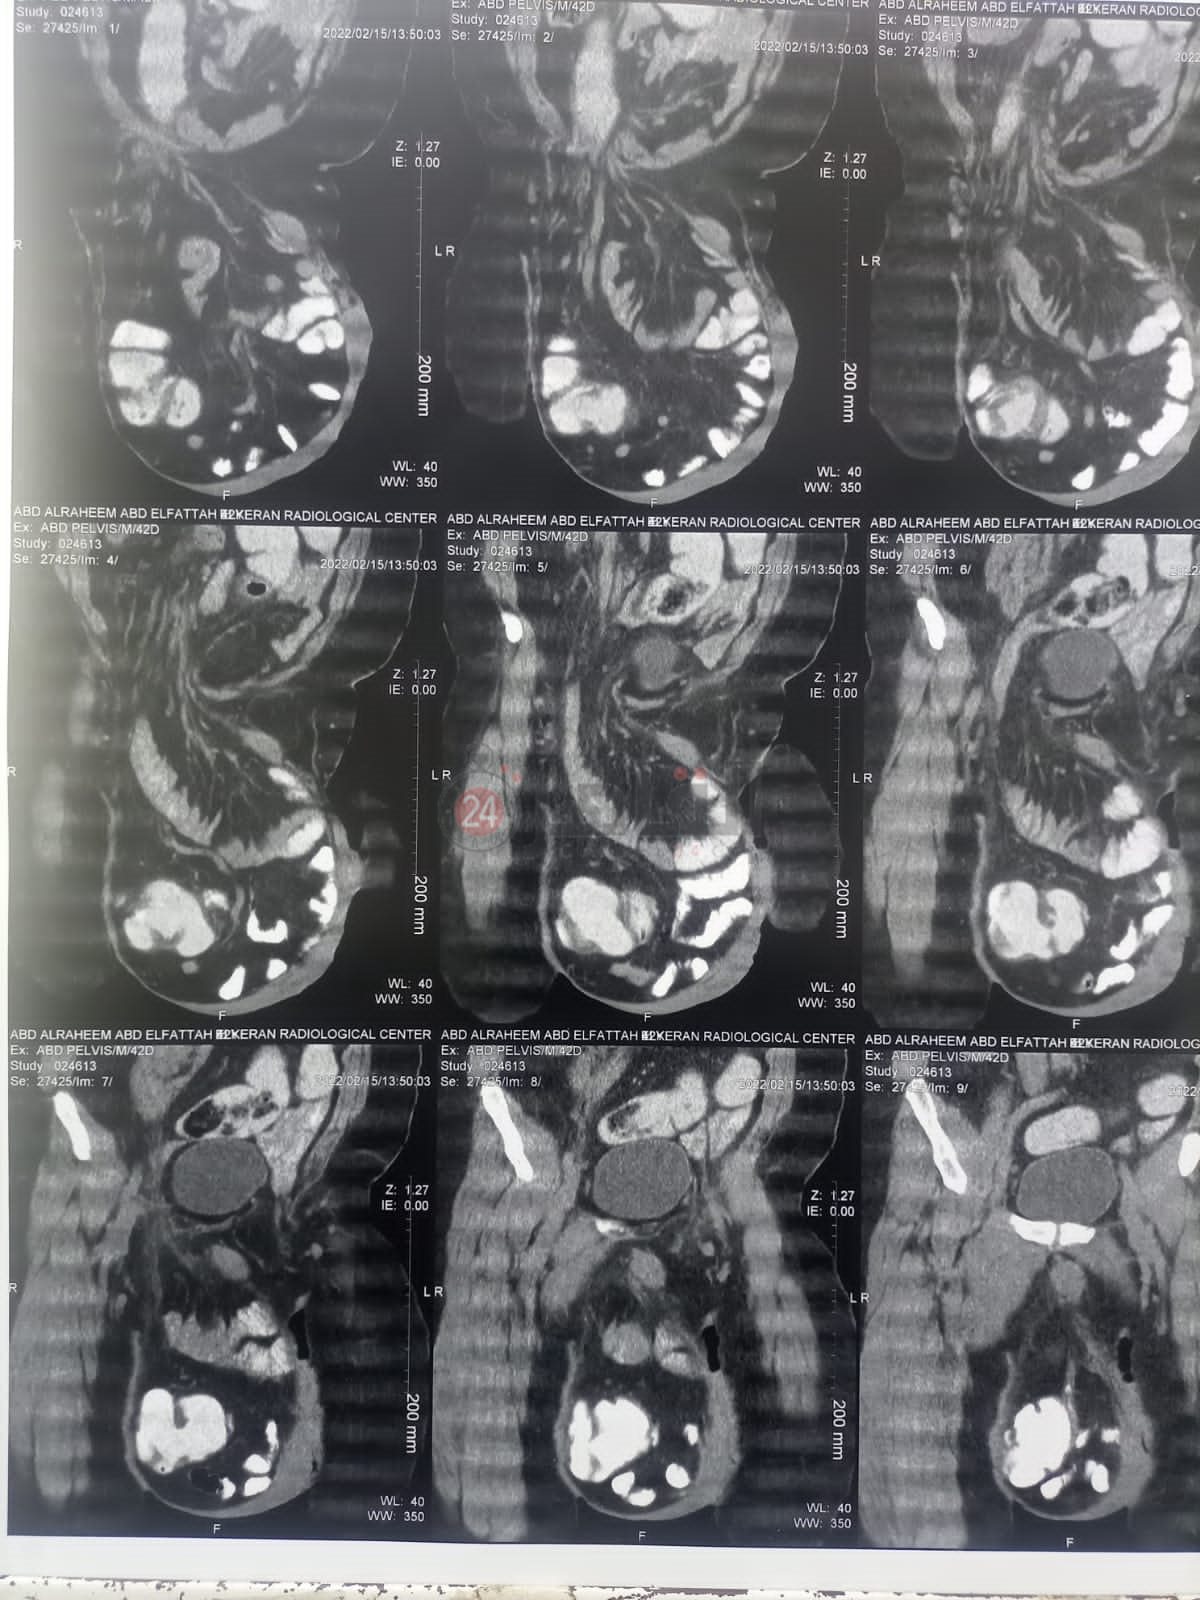

وقال الدكتور محمود القهيوي، أخصائي الجراحة بمستشفى قنا العام لـ القاهرة 24، إن المستشفى استقبل مريضا يبلغ من العمر 40 عاما، يعاني من فتق أربي كبير - ميجا هرينيا- لمدة عام ونصف ومنعه من ممارسة عمله، لافتا إلى أنه جرى عمل الفحوصات اللازمة وتحضير المريض للعملية من خلال إنقاص وزنه على نظام غذائي معين.

وأوضح أن القولون المستعرض والأعور واللفائفي من ضمن مكونات الفتق وتم الحفاظ على الخصية، مؤكدًا أن هذه العملية تعتبر من العمليات الجراحية ذات مهارة وخرج المريض من المستشفى، وتتم المتابعة معه بعيادة الجراحة العامة بالمستشفى.